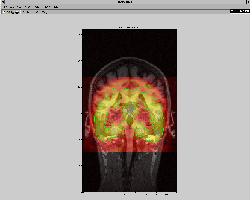

A first order registration can be done by pressing the 'CM alignment' button on the IIO interface, which will register the centres of mass of the two images (Figure 21).

Figure 21: IIO - centres of mass aligned.

\includegraphics[width=0.6\textwidth]{images/iio_2.ps}